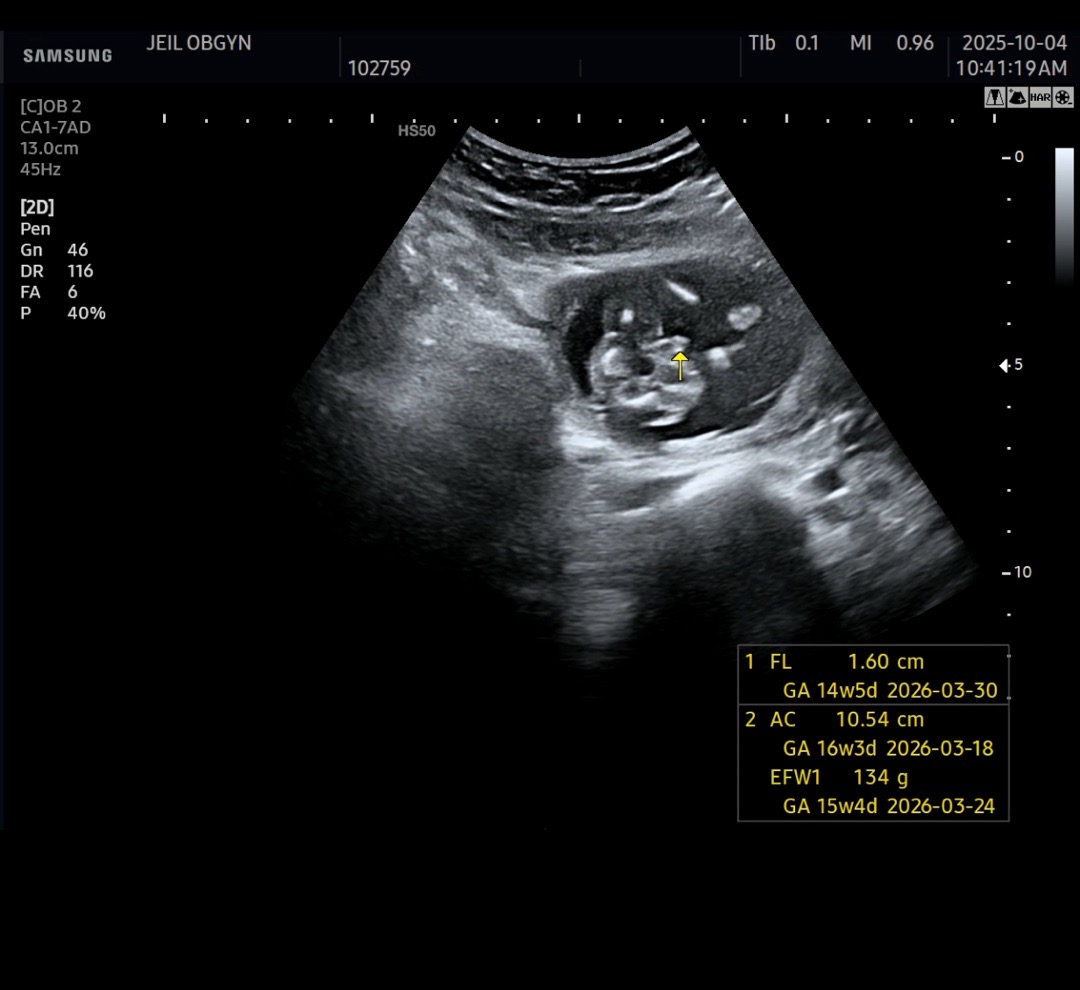

2026년 3월 베동

성별이 궁금해요 ! 아들인가요? 딸인가요?

16주차요 ! ! ! 12주 정밀 초음파에서는 딸인거같다고 했거든요ㅠㅠㅎㅎ갑자기 ㅎㅎ아들인거 같기도 해서요

12주때는 딸인거 같다했는데 ㅎㅎ오늘 가니까 아들같다고 하네요 ㅎㅎ